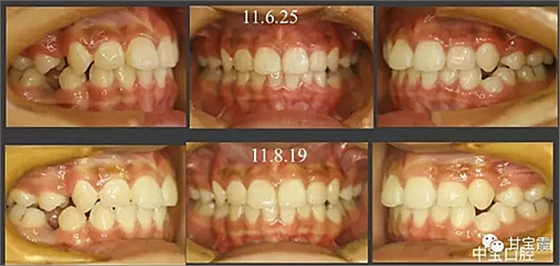

經(jīng)過三年零九個(gè)月的看護(hù),最終戴上了固定矯治器,但是大家不難發(fā)現(xiàn),孩子的牙齒已經(jīng)排齊,上下中線也基本對齊,面型也好看多了,這樣矯正就變得簡單,療程自然縮短,孩子也不遭罪了。

這個(gè)故事告訴我們,只有家長早點(diǎn)把孩子帶給正畸醫(yī)生檢查,才能早期發(fā)現(xiàn)早期治療。起到了事半功倍的效果。矯正以后還不容易復(fù)發(fā),因?yàn)閺?8年的初診到11年戴矯正器這三年多的時(shí)間里,孩子的牙齒是自己長好的。